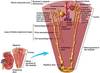

Alternative route to kideny infection

organism?

pyelonephritis

hematogenous

Acute vs. Chronic

pyelonephritis

Acute

the kidney is somewhat enlarged, and discrete, yellowish, raised abscesses are apparent on the surface

neutrophilic infiltrate, suppurative necrosis, and abscess formation

Chronic

chronic tubulointerstitial inflammation and scarring involve the calyces and pelvis

parenchyma shows interstitial fibrosis with an inflammatory infiltrate of lymphocytes, plasma cells, and occasionally neutrophils